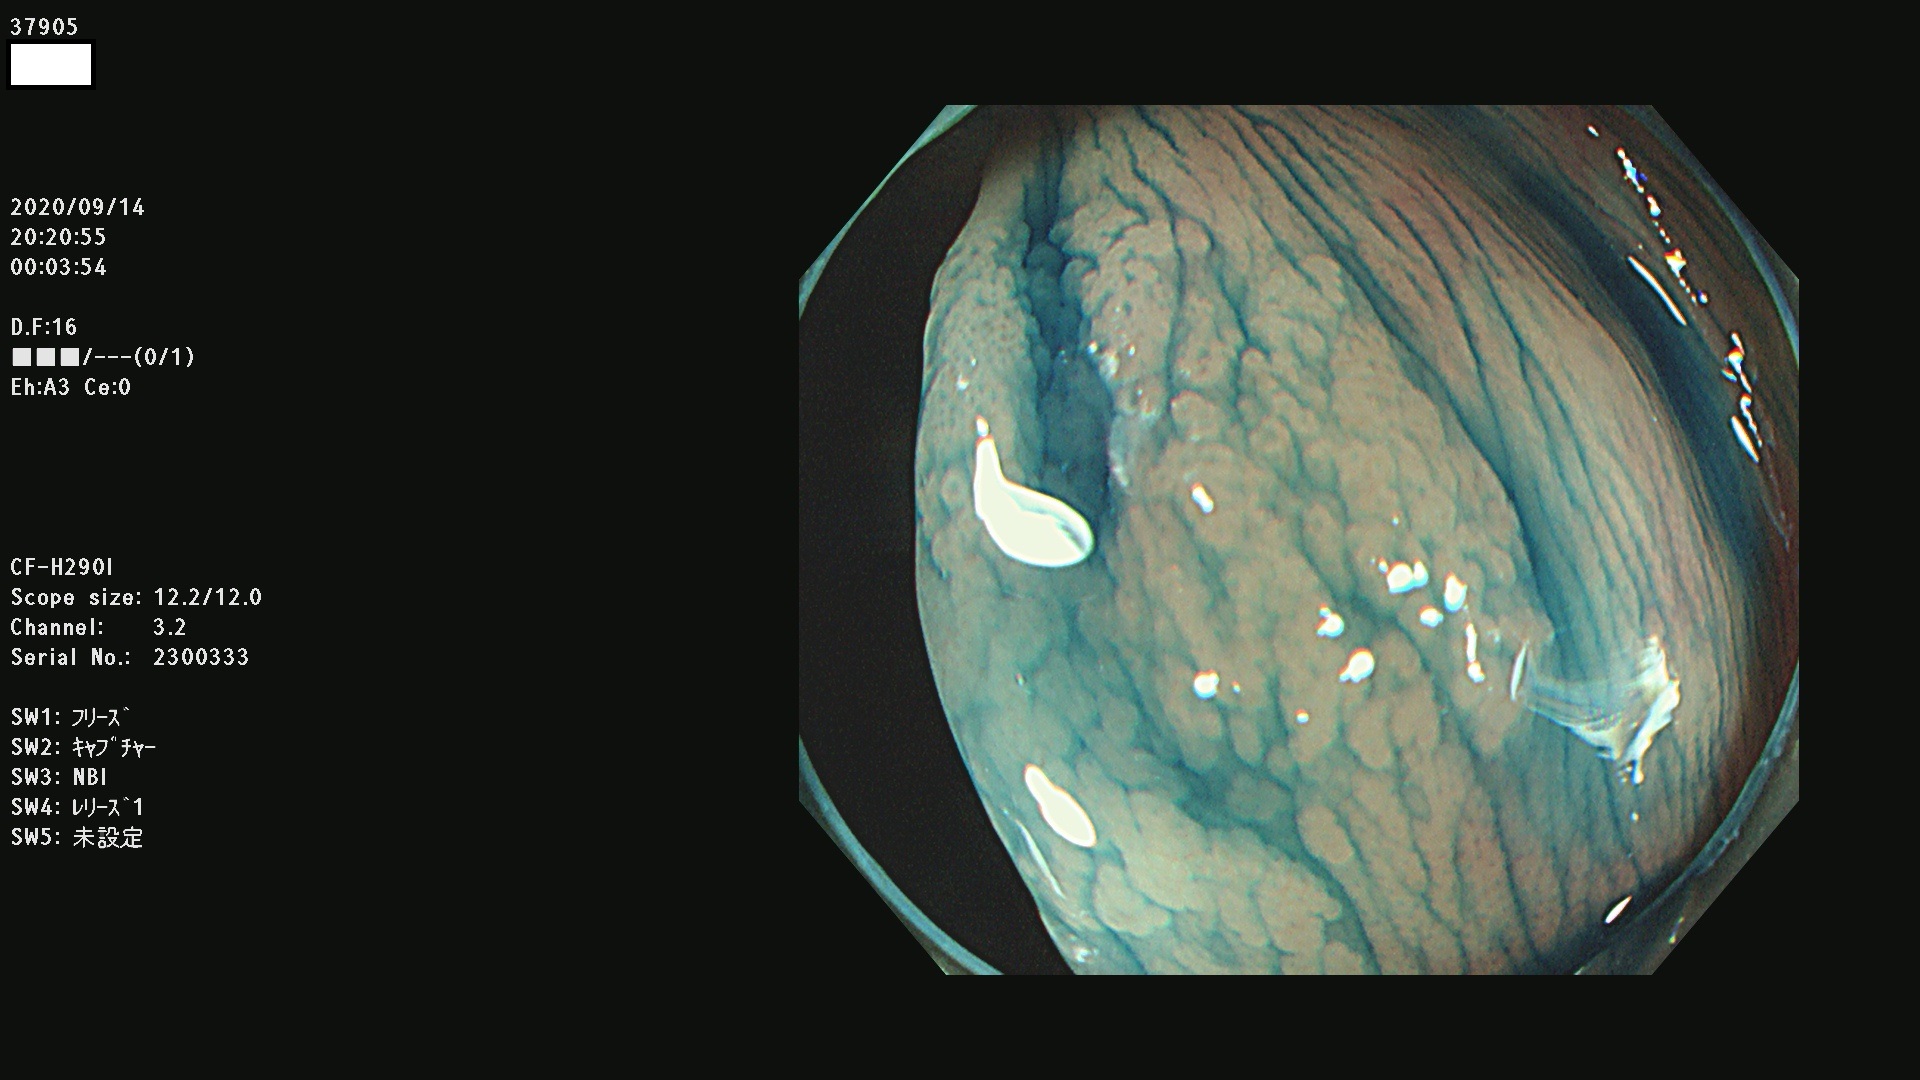

37900 37902 37903 37904 37905 37906 37907 37909 37910 37911 37912 37913 37914 37915 37916 37917 37919 37921 37922 37923 37926 37928 37929 37930 37931 37933 37934 37935 37936 37937 37938(SSAPのみ) 37939 37940 37941 37942 37943 37946 37947 37948 37949 37951 37952 37953(SSAPのみ) 37955 37956 37957(SSAPのみ) 37958(SSAPのみ) 37960 37962 37963 37964 37966 37967 37968 37971 37972 37973 37975 37976 37977 37979 37982 37983 37984 37985 37986 37987 37988 37989 37990 37991 37992 37993 37994 37995 37996 37998 37999

発見困難で危険性の高い平坦型病変(上記100名より抽出)